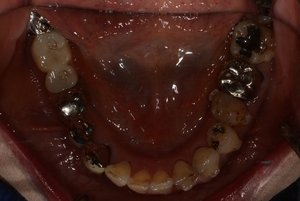

〇ご相談内容:歯並びがよくない〇矯正の種類:マウスピース型矯正「インビザライン」〇治療期間:39週間〇治療費用:44万円(税込)